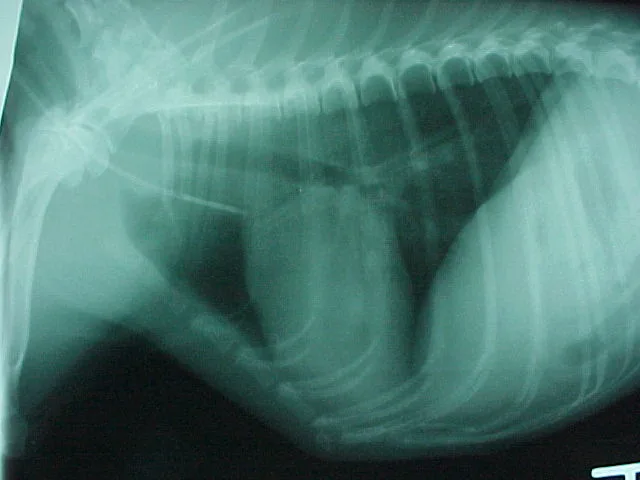

Step 13

Thoracic radiography may be used to assess the location of the tip of the catheter. (Note: This image is not from the same patient as in previous images but illustrates proper site of placement).